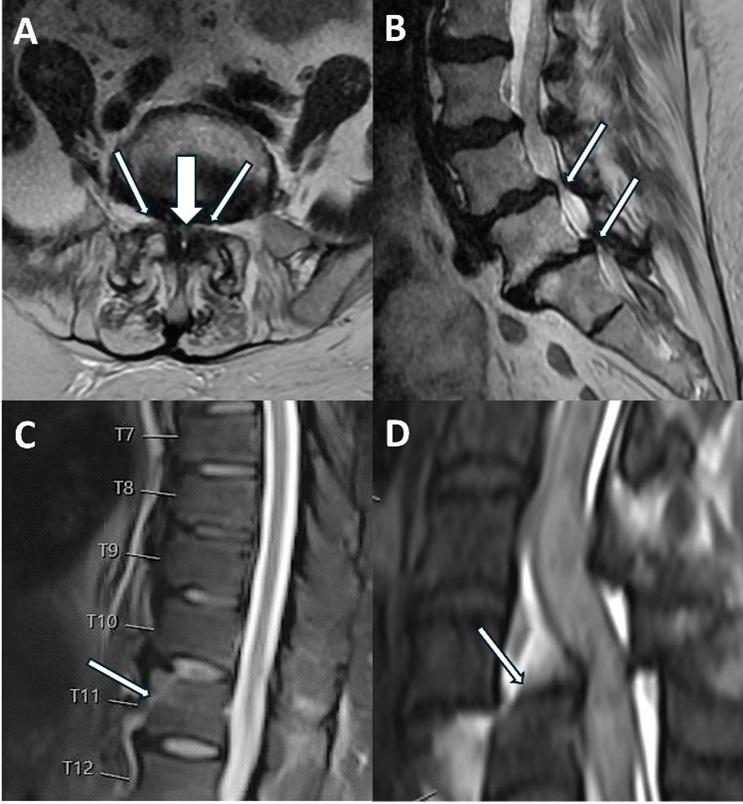

936 Utility of Emergent Spine MRI in the Emergency Department

F Hajibonabi, D Cohen-Addad, F Delgado, P-H Chen, B Fang Wang, S Das, TN Hanna